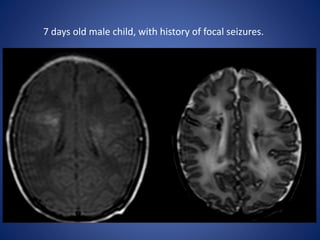

7 days old male child, with history of focal seizures.

DWI ADC

7 days oldmale child, with history of focal seizures.